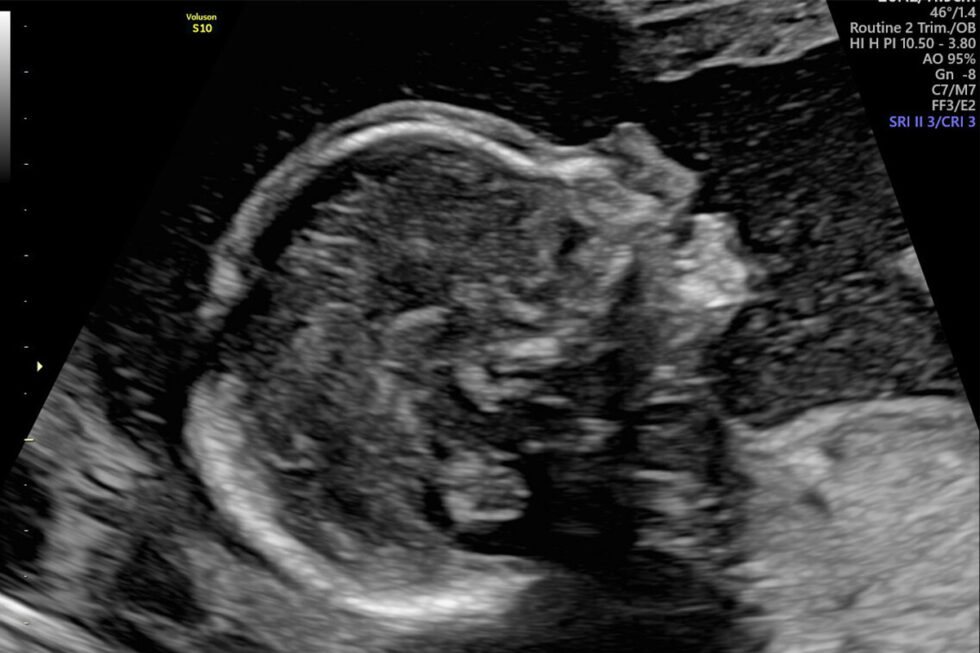

Laten we beginnen met de basis. Beide echo's zijn belangrijke momenten tijdens de zwangerschap, maar ze dienen verschillende doelen. Je kunt ze zien als momentopnames van de baby, maar dan op verschillende momenten in de ontwikkeling.

De 13-weken echo vindt, zoals de naam al zegt, plaats rond de 13e week van je zwangerschap. Een belangrijk doel is om de uitgerekende datum zo nauwkeurig mogelijk vast te stellen. Vroeg in de zwangerschap groeit elke baby namelijk redelijk gelijk, waardoor de meting van de baby op dit moment heel betrouwbaar is.

De 20-weken echo, ook wel bekend als het Structureel Echoscopisch Onderzoek (SEO), is een uitgebreid onderzoek dat plaatsvindt rond de 20e week van je zwangerschap. Dit is een meer gedetailleerde echo dan de 13-weken echo.